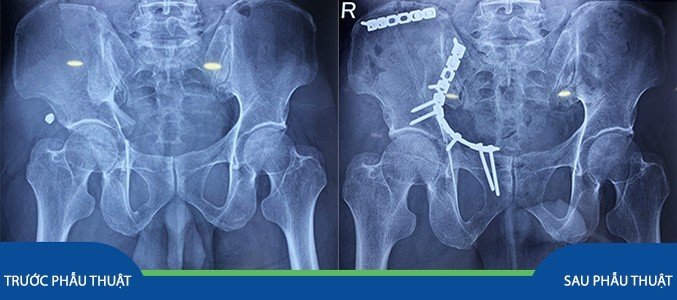

Bệnh nhân H.V.H. (67 tuổi) nhập viện trong tình trạng sốc đa chấn thương sau tai nạn giao thông. Bệnh nhân được người nhà đưa vào cấp cứu tại Bệnh viện Chấn thương Chỉnh hình Nghệ An. Sau khi được sơ cứu và hồi sức chống sốc và thực hiện cận lâm sàng, bệnh nhân được chẩn đoán: Đa chấn thương: Chấn thương ngực kín: Gãy xương sườn II, III bên trái, gãy xương sườn IX, X, XI bên phải/ Gãy xương đòn trái/ Chấn thương khung chậu: Gãy ngành chậu mu, ngồi mu, xương cánh chậu phải, vỡ ổ cối phải, gãy hở 2 mắt cá chân phải. Bệnh nhân được các bác sỹ thực hiện phẫu thuật cắt lọc xử lý gãy hở thì đầu, sau đó được điều trị tích cực chống phù nề, giảm đau và lên kế hoạch phẫu thuật kết hợp xương gãy ổ cối.

Theo bác sỹ Nguyễn Mạnh Linh – Phó trưởng khoa Chi dưới, gãy xương chậu làm thay đổi thể tích khung chậu, có thể gây ra tình trạng chảy máu ồ ạt, dẫn đến tình trạng sốc do giảm thể tích tuần hoàn. Bác sĩ cũng đánh giá đây là một trường hợp nghiêm trọng vì gãy ổ cối và cánh chậu là chấn thương phức tạp, gây mất vững ổ cối và khung chậu, khiến bệnh nhân có nguy cơ mất hoặc suy giảm chức năng đi lại.

Sau thời gian hội chẩn và lên kế hoạch phẫu thuật tỉ mỉ, Ekip phẫu thuật bao gồm: BS. Nguyễn Mạnh Linh – Phó trưởng khoa Chi dưới, BSCKI. Nguyễn Hữu Đức, cùng các bác sỹ và kỹ thuật viên khác đã phẫu thuật kết hợp xương ổ cối và cánh chậu cho bệnh nhân. Ca phẫu thuật thành công mỹ mãn. Một tuần sau phẫu thuật, bệnh nhân có thể tự ngồi được, chức năng thụ động khớp háng bên phẫu thuật đạt được tối đa, bệnh nhân có thể tự ngồi và vận động nhẹ tại giường.

BS. Nguyễn Mạnh Linh cho biết: “Gãy ổ cối là một trong những loại gãy rất khó để có thể nắn chỉnh và kết hợp xương, vì vậy đòi hỏi phẫu thuật viên trong quá trình phẫu thuật phải luôn tập trung cao độ và phải thật tỉ mỉ để có thể hoàn thành cuộc phẫu thuật một cách tốt nhất.”